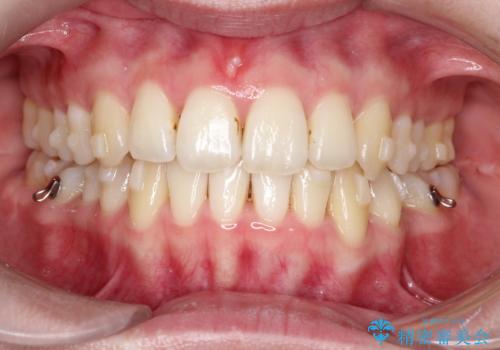

前歯のガタガタと欠損部を改善

- 患者様は、前歯のガタガタ(叢生)と左下5番の欠損部が気になるとのことで来院されました。診断の結果、インビザラインを用いて前歯の叢生を整えながら、左下5番の欠損部にはインプラント治療を計画しました。矯正治療により、歯並びを改善すると同時に、噛み合わせのバランスも向上させることを目標としました。矯正期間とインプラントの治療計画を並行して進めることで、患者様のご希望に応えるプランを立てました。

前歯の叢生改善のため、インビザラインによる透明で目立たない矯正装置を使用しました。治療中は、歯の移動による負担を最小限に抑えつつ、歯列全体のバランスを考慮して進めました。左下5番の欠損部には、矯正終了後にインプラントを埋入し、自然で機能的な咬合を回復しました。治療期間中、患者様には装置の正しい装着と日々の清掃を徹底していただき、歯肉やインプラント周囲の健康を保つようサポートしました。結果として、美しい歯並びと快適な噛み合わせを両立させることができました。